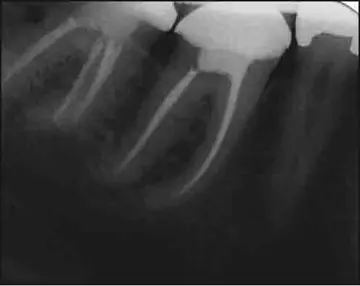

شکست درمان کانال ریشه(۲) (بخش پایانی)

پرکردن بلند کانال ریشه: پرکردگی بیش‌از 2میلی‌متر فراتر از آپکس رادیوگرافی اغلب به‌علت وجود تحلیل التهابی آپیکال، آپکس با تکامل ناقص یا اندازه‌گیری غلط طول کارکرد و فایل‌کردن از ورای فورامن آپیکال صورت می‌گیرد.